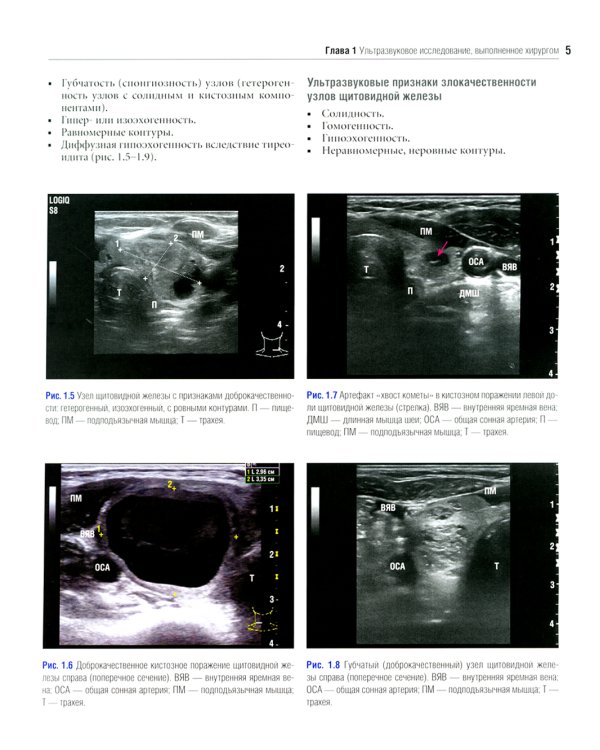

Данное издание представляет собой великолепно иллюстрированный хирургический атлас. В нем рассмотрены методы ультразвукового исследования шеи, молекулярно-генетическое тестирование пациентов с узловыми образованиями в щитовидной железе, робот-ассистированные хирургические методы, техника эндоскопических операций при эндокринных опухолях, хирургия при рецидиве заболевания, аутотранснлантация и криоконсервация околощитовидных желез, адреналэктомия при метастазе в надпочечнике, хирургия нейроэндокринных опухолей тонкой кишки и их метастазов в печени. «Атлас эндокринной хирургии» состоит из 4 частей: «Хирургия щитовидной железы», «Хирургия околощитовидных желез», «Хирургия надпочечников», «Хирургия опухолей поджелудочной железы и карциноидов». Всего в издании 29 глав, подготовленных сотрудниками экспертных факультетов ведущих медицинских школ США, Европы и Азии. Каждая глава состоит из разделов, в которых описаны общие сведения, показания и противопоказания, оценка риска, алгоритм принятия решений и планирование вмешательства, необходимое оборудование и материалы, хирургические техники, результаты лечения, осложнения и последующее наблюдение, а также даны советы и предостережения авторов. В книге много информации, которой нет в других источниках. Наряду с многочисленными фотографиями, сделанными в ходе операций, а также данными, полученными при различных методах визуализации, приведено значительное количество иллюстраций и видеоматериалов, демонстрирующих хирургическую технику или обследование. Издание предназначено практикующим врачам в области эндокринной хирургии, специалистам в смежных областях медицины и студентам медицинских высших учебных заведений.| Издательство | Логосфера |